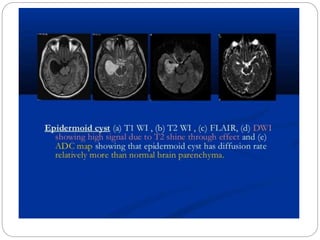

Epidermoid versus Arachnoid cyst

 Epidermoid composed of keratin, debris and solid

cholesterol

 Provide hindrance to diffusion of H2O molecules

 Epidermoid is seen as bright lesion on DWI

 Arachnoid cyst is clear CSF containing cyst, it will

not be bright on DWI will be same as CSF in the

signal intensity

 DWI can detect a residual epidermoid